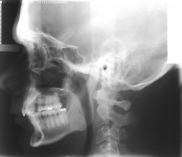

Chirurgia dentystyczna zajmuje się leczeniem operacyjnym jamy ustnej, zębów i tkanek otaczających. Znaczna większość zabiegów z zakresu chirurgii stomatologicznej jest wykonywana w znieczuleniu miejscowym .Dental Park jako jeden z nielicznych oferuje również wykonywanie zabiegów pod narkozą. Najpowszechniejszym zabiegiem z zakresu chirurgii stomatologicznej jest usunięcie zęba czyli ekstrakcja, ale chirurgia stomatologiczna to także zaawansowane zabiegi jak implanty czy wyłuszczanie torbieli kości.

Chirurg stomatolog posiada wieloletnie doświadczenie i w swojej karierze spotkał się z najtrudniejszymi przypadkami. W gabinecie wykonywane jest usuwanie zębów w znieczuleniu miejscowym oraz w narkozie co zapewnia całkowicie bezbolesny zabieg. Pracownia stomatologiczna usuwa zęby mądrości, złamane korzenie. Bardzo często naszymi pacjentami są osoby, które usuwają zęby ze wskazań ortodontycznych. Wykonujemy również zabiegi odbudowy kości jako przygotowanie do leczenia implantologicznego. Nasi pacjenci mogą zawsze liczyć na szybką pomoc w przypadku ropnia, ostrego bólu lub urazu. Chirurg stomatolog zajmuje się wszystkimi nawet najbardziej skomplikowanymi przypadkami.